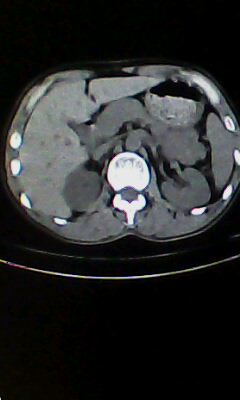

胰尾部占位?

未见明显异常。“胰尾占位”为肠管

口服造影剂是必须的